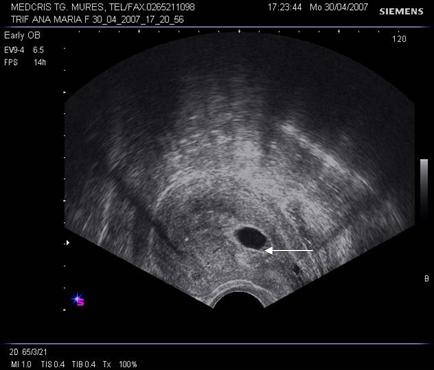

8.Sarcina si dispozitivul intrauterin

Pacienta purtatoare de IUD va fi examinata pentru a stabili locul dispozitivului in cavitatea uterina. Daca acesta a fost evacuat sarcina va continua fara risc. Daca IUD este inca intracavitar, va trebui decis daca trebuie extras in functie de pozitie si de varsta sarcinii.

Ecografic, dispozitivul apare ca o structura ecogena cu forma variabila, localizat alaturi deasupra sau sub sacul gestational, eventual in canalul cervical.

Daca dispozitivul intrauterin prin pozitia sa nu poate fi extras, continuarea sarcinii poate fi grevata de cresterea riscului de avort, infectii, perforatii, nasteri premature. Prezenta asocierii IUD cu sarcina nu constituie indicatie de avort si nu creste riscul de anomalii fetale.

La pacientele cu teste pozitive si IUD prezent se va cerceta cu grija regiunea anexiala bilateral pentru a exclude o sarcina ectopica.

Fig nr. 90. Dispozitiv intrauterin dislocat in col, la o sarcina de 17 saptamani